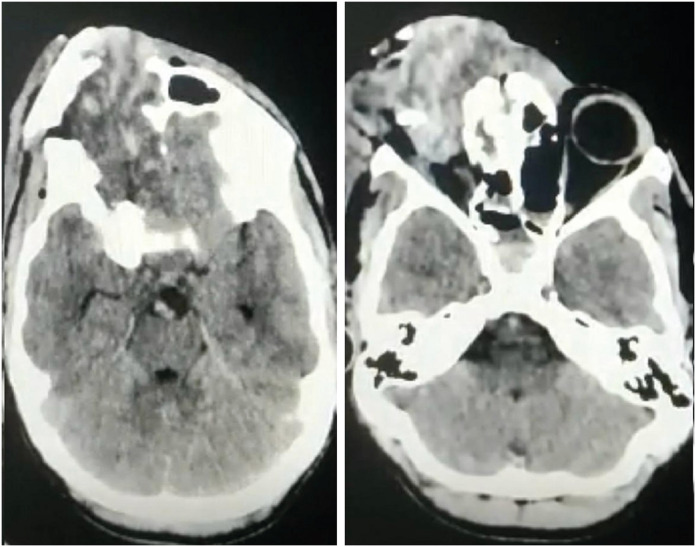

Farm-related head injuries are a significant cause of death and disability in rural households. Traumatic brain injury can result in long-term disability. The use of modern farming equipment has increased in the Indian agricultural sector over the last few decades. Machines such as threshers and winnowing devices can cause open skull fractures or scalp avulsions, while the fall of heavy tools may lead to severe head trauma. Farm animals such as bullocks and horses can also inflict traumatic brain injuries with their pointed horns, through trampling, kicking, or rarely biting. We present a case series of four patients who sustained head injuries due to farm-related accidents. All patients sustained compound cranial fractures with underlying brain parenchymal injuries, and three of them achieved complete recovery following timely medical intervention.